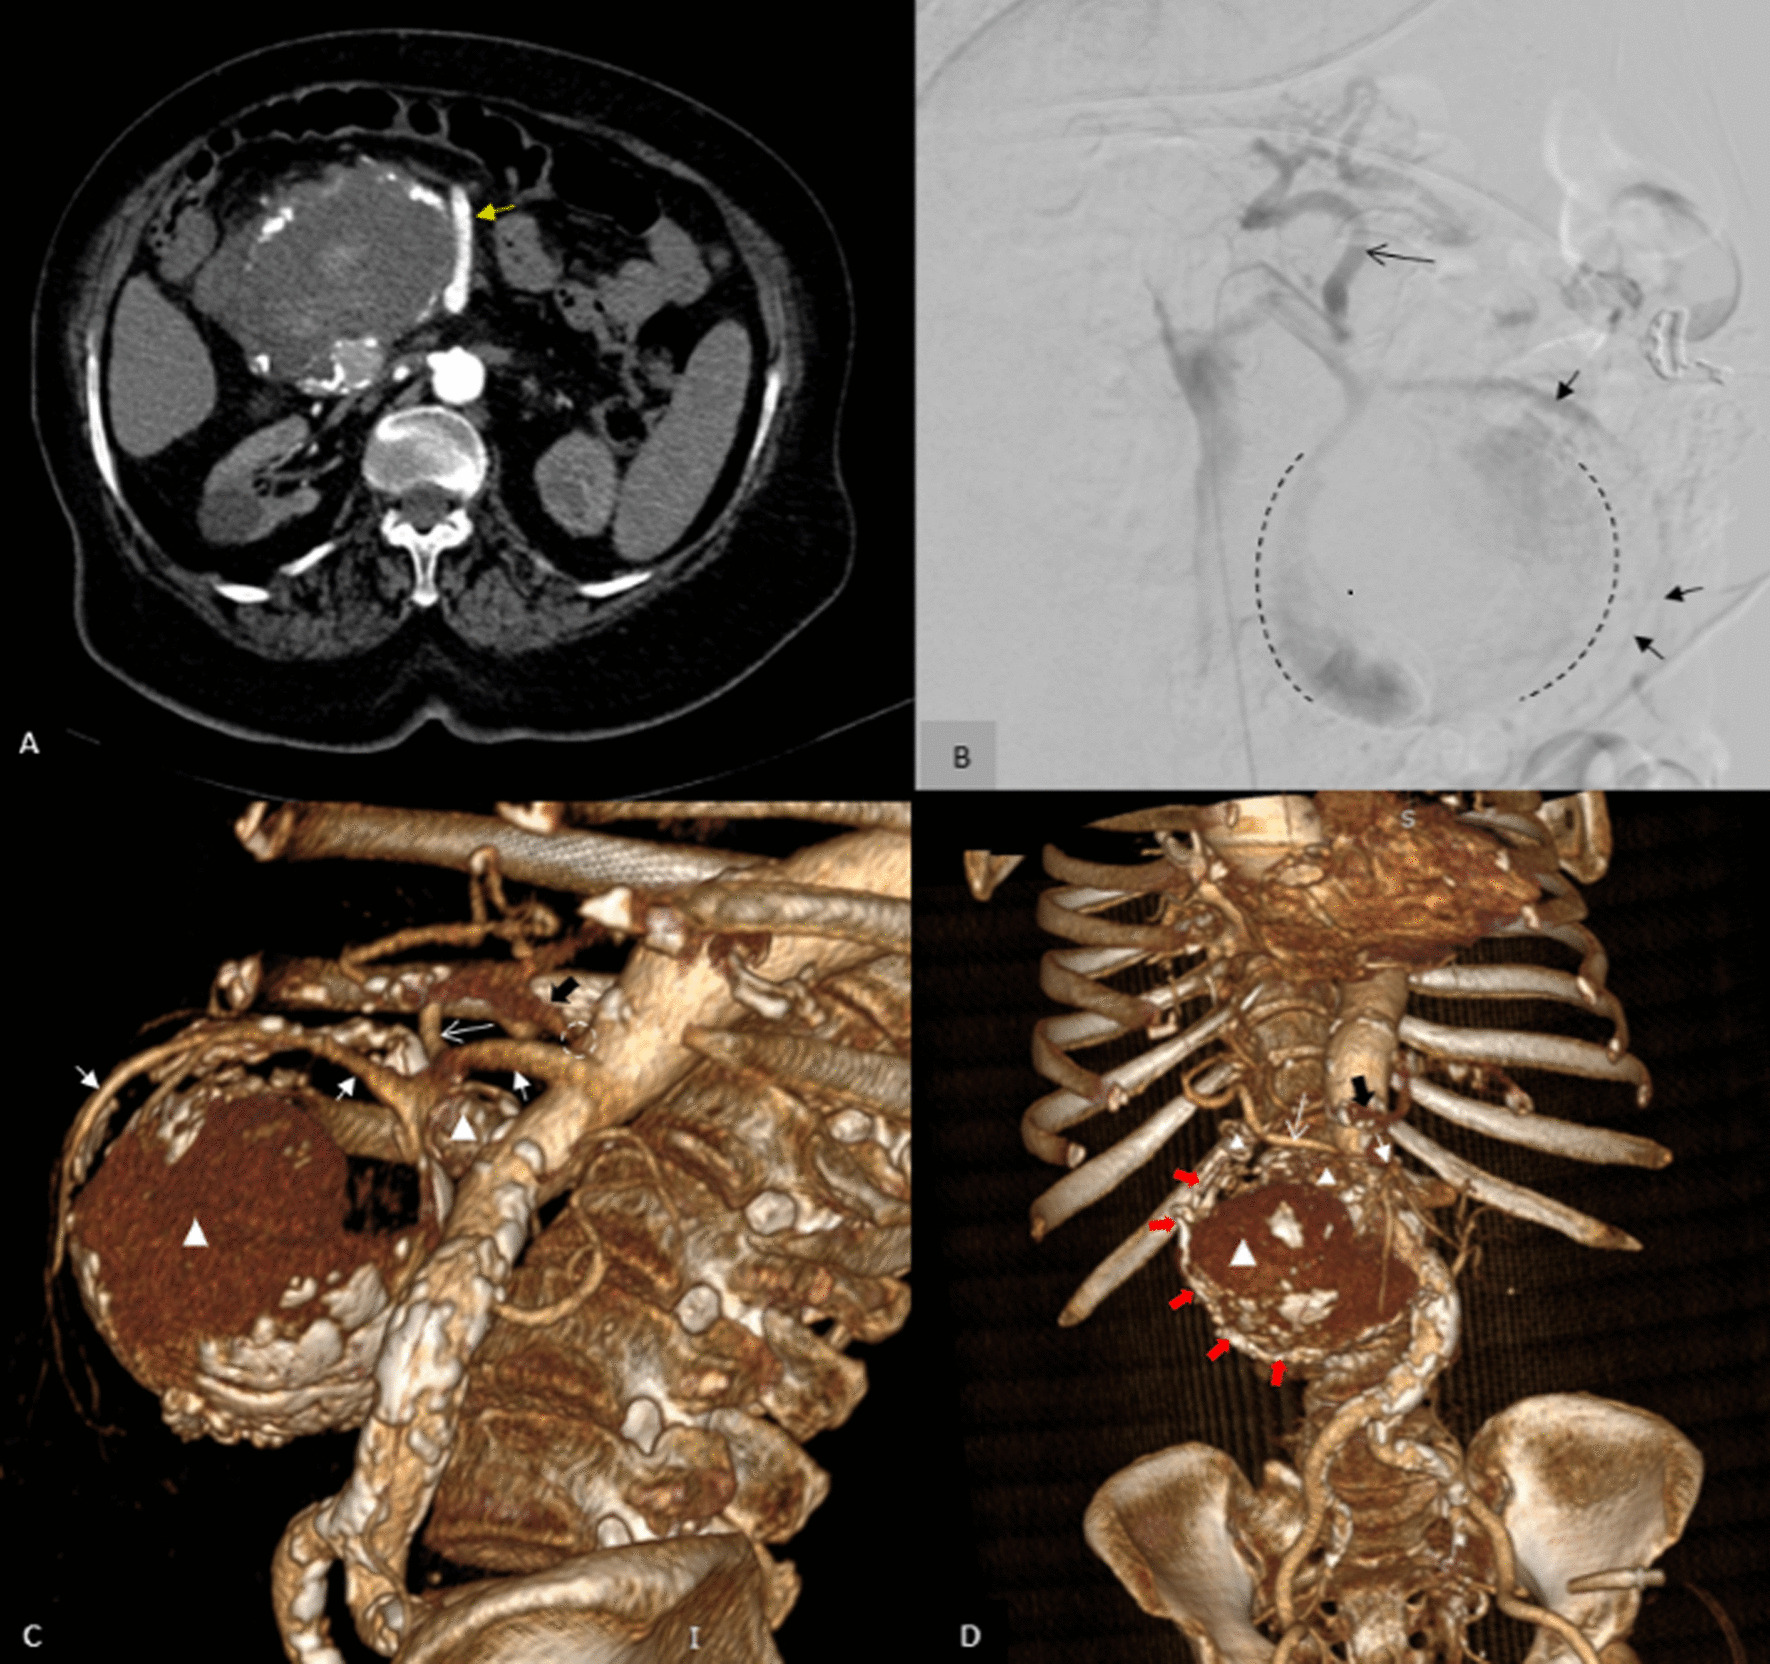

In the non-contrast CT that was done before the computed tomography angiography (CTA), there was a huge mass (14 × 10 × 9 cm) with peripheral discontinuous calcification near the head of the pancreas extending superiorly to the subhepatic region and inferiorly medial to the cecum and causing severe compression on D2 and D3 portion of the duodenum and the common bile duct (CBD). Moreover, marginal hyperdense crescent areas were present (Fig. 2A–C). After contrast injection in the arterial phase of CTA, the mass had a density like an aorta and originated superiorly from the posterior surface of the proximal portion of the SMA. The aneurysm was inferiorly connected to the tortuous atherosclerotic vessels around the head of the pancreas. These vessels superiorly originated from the gastroduodenal artery. All arterial branches supplying the bowel loops originated from own SMA, not from this aneurysm. These findings suggest that the huge aneurysm originated from the inferior pancreaticoduodenal artery, which was connected to SMA on one side and to anterior and posterior pancreaticoduodenal arteries on the other (Figs. 2D, 3A, C, D).

There was mural thrombosis in the aneurysm, which was accompanied by a linear extension of intraluminal contrast through the mural thrombosis, indicating a thrombosis fissuration sign (Fig. 2E). Discontinuous calcification of the aneurysm’s wall was present, and there were areas of focal bulging of the aneurysm’s lumen to the surrounding mesenteric fat, associated with mild stranding and minimal fluid in these areas. Two smaller aneurysms (2.5 × 2.5 cm and 1.5 × 1.2 cm) were also seen adjacent to the superomedial margin of the huge aneurysm, originating from the posterior branch of the gastroduodenal artery (superior posterior pancreaticoduodenal artery) (Figs. 2E, J, 3C, D). A significant narrowing at the origin of the celiac trunk was noted due to diaphragmatic crura compression, indicating median arcuate ligament syndrome (Figs. 1D, 2D, G, 3C).

So, conventional angiography (CA) was done (Fig. 3) to evaluate the precise anatomy of aneurysms, confirm CTA findings, and to perform transarterial embolization (TAE), but CA was terminated early due to some reasons. First of all, it was impossible to interpret digital subtraction angiography (DSA) images due to blurring caused by the patient’s coughing. More significantly, the patient experienced dizziness following a puncture of the femoral artery. When she became dizzy, her blood pressure was 90/60, and her heart rate was 100. Fortunately, with close observation, minimal hydration therapy (up to 200 cc of fluid), and leg elevation, her vital signs quickly returned to normal. Her hemodynamics had stabilized after three hours, and hemorrhagic shock was ruled out. Her symptoms were assumed to be the result of reflex syncope brought on by coughing and arterial puncture. After the patient’s blood pressure and heart rate returned to normal, the angiographic procedure could be completed while she was under general anesthesia. However, we were leaning towards the surgical option due to the lack of patient and family consent for general anesthesia to perform supplementary angiography.